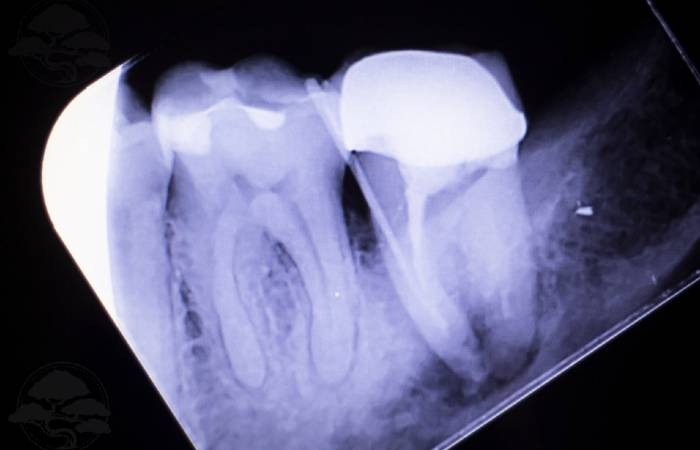

A dental crown is a cap shaped like a tooth that is fitted over your existing tooth. This permanent solution is designed to mimic the look, feel, and function of a natural tooth once it is securely in place. Dental crowns come in three primary types: metal crowns, porcelain crowns, and composite resin crowns.

A crown may be necessary when a tooth is chipped, broken or has a weak structure that cannot be repaired with a filling. In order to keep the natural tooth as long as possible a crown can help to protect the existing tooth from further damage for as long as possible. When a crown is no longer viable, it may be appropriate to extract the tooth.

Broken Tooth

If a chipped, cracked or broken tooth is not treated over time the issue can get worst causing sensitivity and in situations where the tooth is cracked or broken the nerve can become exposed.